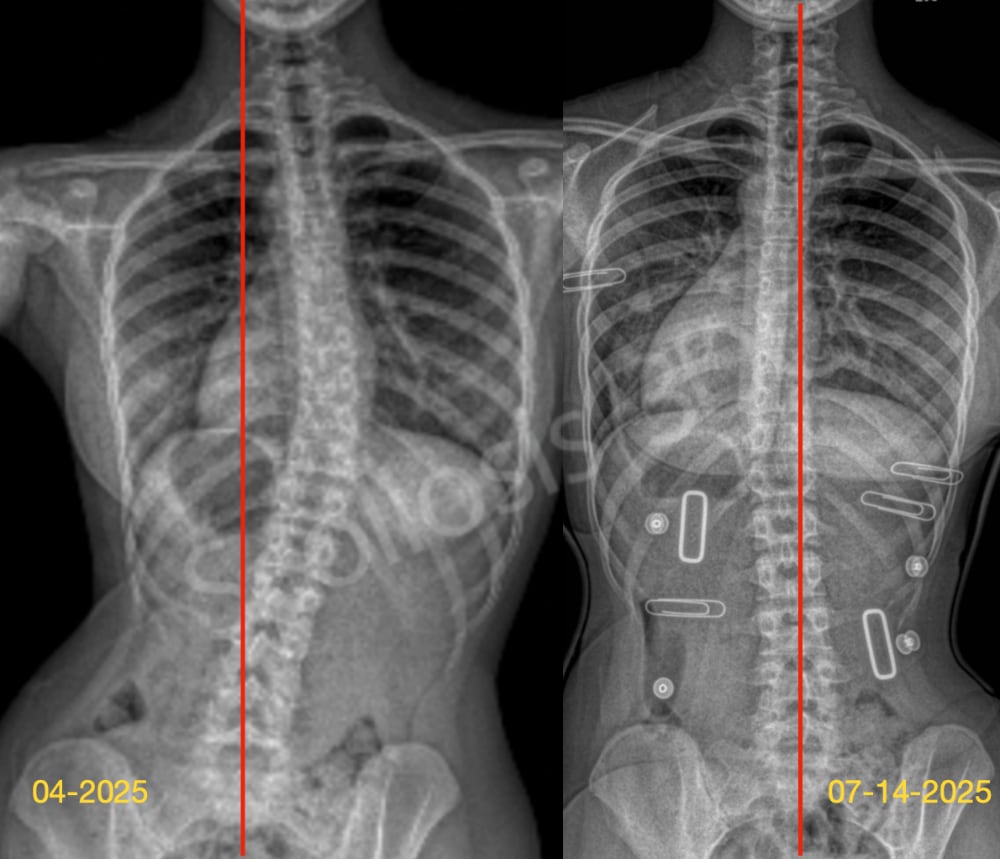

كيف تمنع فشل حزام اعوجاج العمود الفقري وتحصل على نتائج مؤكدة تصل إلى% 95 يعاني بعض المراهقين من اعوجاج العمود الفقري مجهول السبب (Adolescent Idiopathic Scoliosis – AIS)، وغالبًا ما يُوصى باستخدام حزام طبي

حزام اعوجاج العمود الفقري :احتياطات أساسية يومية أثناء الأستخدام لنتائج مؤكدة تصل إلى 95% يُعد حزام اعوجاج العمود الفقري من أهم وسائل العلاج غير الجراحي للأطفال والمراهقين المصابين باعوجاج العمود الفقري. ويهدف الحزام إلى